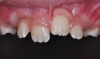

Periodontal soft-tissue scars or deformities have been reported when comparing an impacted maxillary central incisor with its homologous non-impacted counterpart (Figure 19).9,21

Fig 19. Gingival esthetic difference can be noticed in the impacted maxillary right central incisor as compared to the homologous tooth.

Figure 19